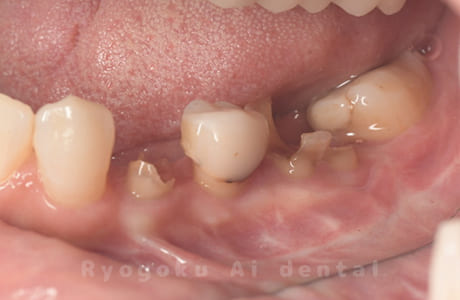

Case14

- 抜歯原因

- 重度カリエス

- 治療内容

- クラウンレングスニング治療

- 治療費用

- 44,000円

他院で抜歯と言われた、とのことでご来院された患者さまです。クラウンレングスニングを行い、保存致しました。大変満足して頂けました。